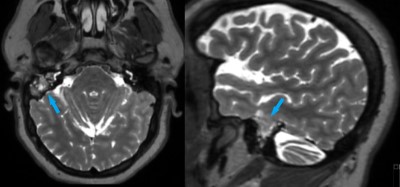

This is a 28 year old female who presents with complaint of right-sided hearing loss and sense of fullness within her right ear.

Her exam is consistent with conductive hearing loss in right ear.